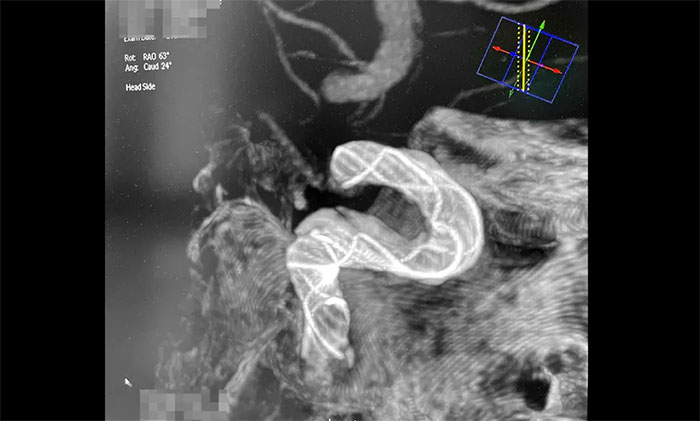

术中,席刚明教授、王贵平博士克服血管迂曲困难,经过多次尝试,多次球囊扩张、“按摩”后,最终顺利释放密网支架至左颈内动脉眼动脉段、左颈内动脉床突段、左颈内动脉海绵窦段。造影及3D造影见,动脉瘤瘤内造影剂明显滞留,左颈内动脉、左大脑前动脉显影可,载瘤动脉通畅,获得了理想的血管重建。复查造影,左颈总动脉造影见左颈总动脉、左颈内动脉、左大脑前动脉显影可。CT见支架打开贴壁满意,XperCT未见颅内出血,手术圆满完成,顺利拆除“不定时炸弹”并打通大脑生命线。

▲ 顺利拆除“不定时炸弹”